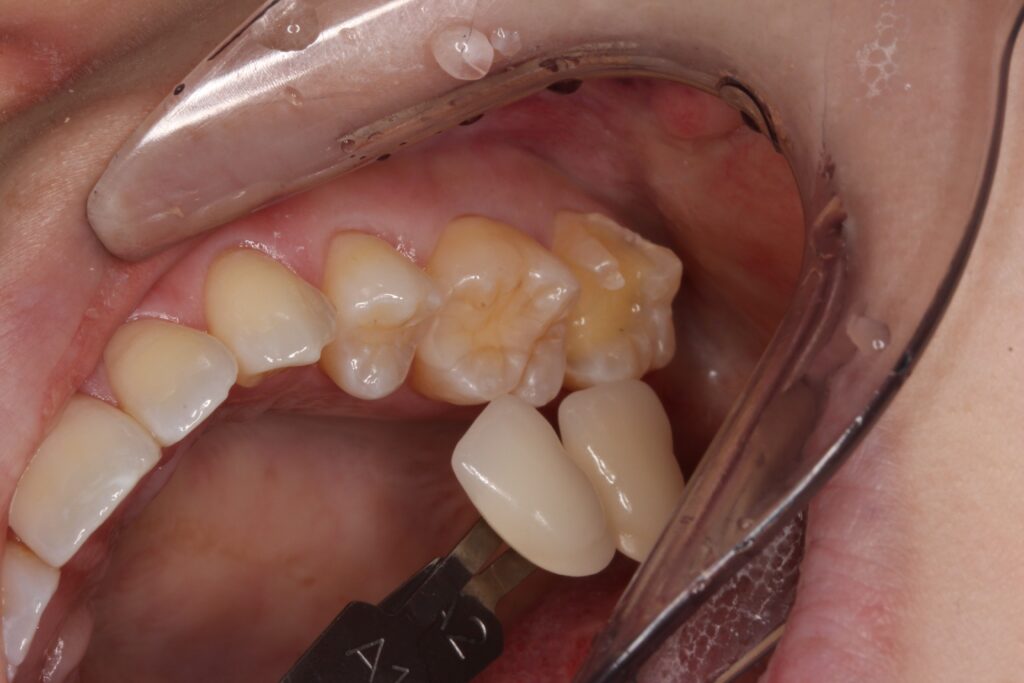

歯の形を整えて歯型を取ります。

歯の色を写真で記録します。

人それぞれ歯の色は違います。

その方に合った歯の色に仕上げます。